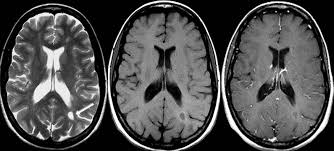

Déficit de atención con hiperactividad: hallazgos en neuroimágenes

La resonancia magnética muestra reducción del volumen de diversas estructuras cerebrales en niños con la afección, pero no en los pacientes adultos. Podría interpretarse como un retraso en la maduración cerebral. The Lancet Psychiatry, 15 de febrero de 2017